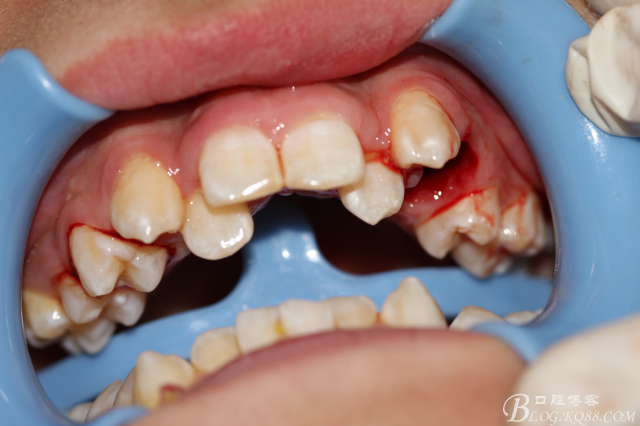

2.術(shù)中口內(nèi)照片